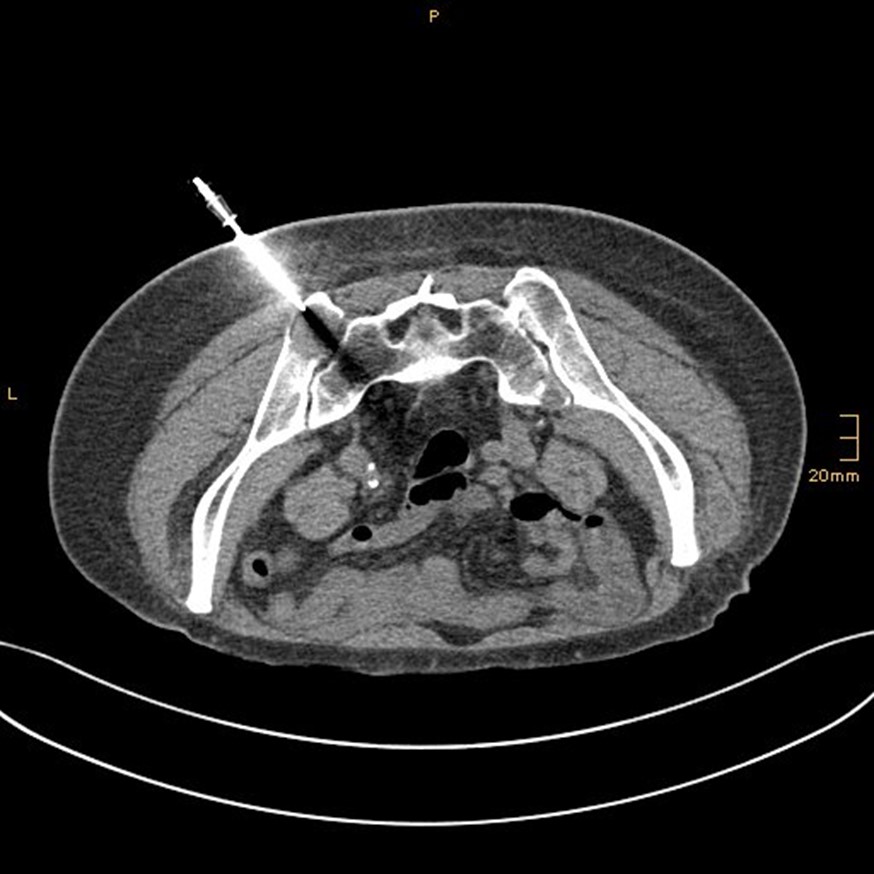

Tumorablationen (RITA, RFA, MWA)

Wir führen minimal-invasive Thermoablationen von Lebertumoren, z.B. bei Leberkrebs oder Lebermetastasen, und von Nierentumoren durch. Auch Lungentumore und Knochentumore sind behandelbar. Wir verwenden Radiofrequenz- oder Mikrowellen-Technik. Die Mikrowellenantenne in Form einer Nadel wird CT-gezielt während einer Kurznarkose zum Tumor vorgeführt. Über diese Sonde wird die Tumorregion erhitzt und der Tumor verkocht. Bei unkompliziertem Verlauf wird die Patientin oder der Patient über Nacht stationär überwacht und dann nach Hause entlassen.